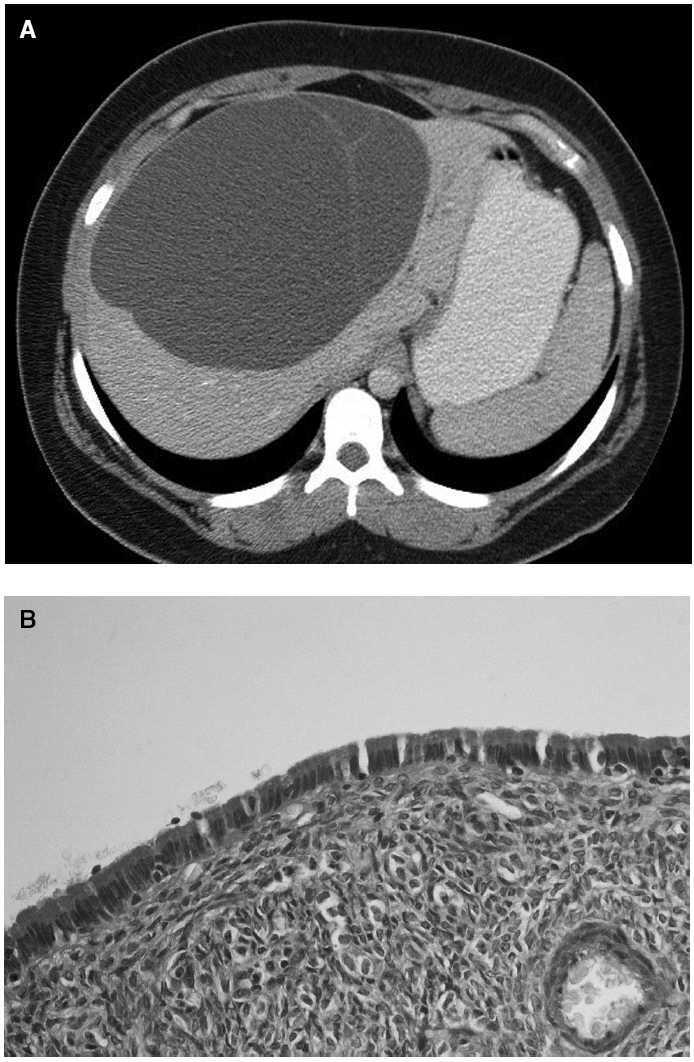

Fig. 2. A: corte axial de la tomografía helicoidal computarizada. La lesión, quística, de gran tamaño, se encuentra dividida por la presencia de un fino septo que la cruza anteroposteriormente. El lóbulo hepático izquierdo se encuentra prácticamente atrófico. B: detalle histológico. Cistoadenoma mucinoso revestido internamente por epitelio cilíndrico simple, PAS positivo, resistente a amilasa, sin atipia (amilasa, ×40).

Mujer de 24 años de edad, sin antecedentes de interés, que consultó por molestias inespecíficas en el hipocondrio derecho y plenitud posprandial sin otra sintomatología acompañante. A la exploración física tan sólo se apreciaba un tinte subictérico conjuntival, y en la exploración abdominal, hepatomegalia de 3 cm desde reborde costal mínimamente dolorosa. Como hallazgos de laboratorio descataban: hiperbilirrubinemia discreta (bilirrubina total, 3,5 mg/dl; directa, 2,56 mg/dl), aumento de la fosfatasa alcalina (560 mg/dl) y aumento de transaminasas (GPT, 236 mg/dl; GGT, 362 mg/dl). En la ecografía se objetivó una masa quística, dependiente de lóbulo hepático derecho (LHD), de aproximadamente 16 cm de diámetro, con finos septos en su interior. La tomografía computarizada helicoidal (TCH) mostró una masa bien delimitada, de naturaleza quística asentada sobre el LHD, sin dilatación de las vías biliares intrahepáticas o extrahepáticas (fig. 2). Las muestras de laboratorio de hemaglutinación y látex para descartar hidatidosis resultaron negativas. Se hizo un abordaje mediante una laparotomía subcostal bilateral y se comprobó la presencia de la masa anteriormente descrita que ocupaba casi la totalidad del LH. Se practicó una colangiografía intraoperatoria en la que no se apreció compromiso de la vía biliar intra/extrahepática ni dilatación significativa de ella. El líquido intraquístico era seroso oscuro, acelular en las muestras remitidas para estudio citológico intraoperatorio. Asimismo, en la biopsia intraoperatoria de la pared quística no aparecieron signos de malignidad. Se realizó una exéresis completa de la tumoración y también una colecistectomía. El informe patológico confirmó la naturaleza de la lesión; se trataba de una tumoración quística de paredes fibrosas, con algún septo fino, cuya superficie estaba revestida por un epitelio cilíndrico simple, PAS positivo y PAS-diastasa resistente. El diagnósitco final fue cistoadenoma hepatobiliar de tipo mucinoso.